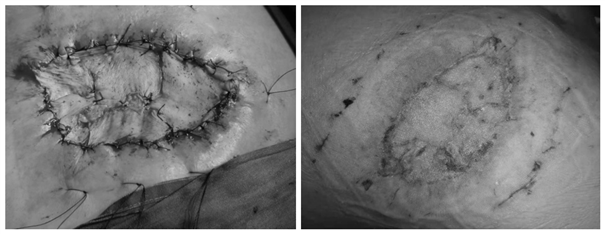

黎跃华主治医师接诊患者后,仔细询问病情,查看患者既往检查结果,根据患者血象极高(超过30×109/L),分泌物培养结果为金葡菌感染,并继发脓毒症综合征引起了左心功能衰竭的病情,诊断为肩背部坏死性筋膜炎(俗称肩背部恶疮,如图1所示)。紧急术前讨论后,组长王志东副教授认为病人因为肩背部恶疮继发脓毒综合征,需急诊手术,不然会发展为脓毒性休克,丧失手术抢救的最佳时机。知情同意签字后,积极联系麻醉科手术室,入院当天急诊对病人成功实施了全身麻醉下皮肤及皮下组织筋膜清创封闭创面负压吸引术。术后病人脓毒感染症状迅速减轻,心功能不全症状基本消失,病情很快缓解。一周后再次彻底清除坏死组织,行清创封闭创面负压吸引术。之后的一周创面长出新鲜的肉芽组织,同时从患者腰背部取薄中厚皮片,移植到左肩背部创面。一周后移植皮片完全存活,病人痊愈出院。

创面修复专家黎跃华主治医师介绍,坏死性筋膜炎多在糖尿病及免疫功能低下的病人中易出现,这是一种快速出现皮下组织和筋膜坏死为特征的软组织感染,常伴有全身中毒症状,容易继发感染休克。肩背部的坏死性筋膜炎常易与疖肿及痈混淆,如果发病早期没有被及时诊断,也不重视病情,不积极手术彻底清创,病人可因病情迅速进展,导致感染性休克而危及生命。传统的坏死性筋膜炎治疗采用十字切开引流换药,患者痛苦大,组织渗出多,大多需要进行6次左右的反复手术,皮肤缺损较大时常需换药数月,给患者及其家属带来极大的困扰,也给病人身心和经济带来很大痛苦和压力。此次新技术的实施,待新鲜的创面长出后再行皮肤移植修复。这样不但能迅速控制感染,显著缩短手术治疗次数为3次,还大幅度缩短住院时间,也减轻患者自身的痛苦和经济压力。